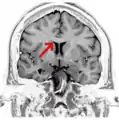

Coronal T2 (grey scale inverted) MRI of the brain at the level of the caudate nuclei emphasizing corpus callosum- Tractography of Corpus callosum